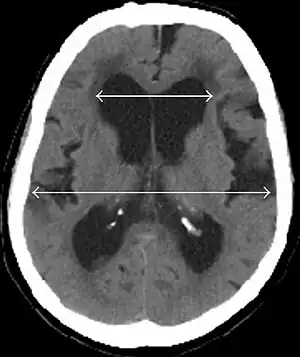

Evan's index is the ratio of maximum width of the frontal horns to the maximum width of the inner table of the cranium. An Evan's index more than 0.31 indicates hydrocephalus.[2]

• Imaging from magnetic resonance imaging (MRI) or computed tomography (CT) is needed to demonstrate enlarged ventricles and no macroscopic obstruction to cerebrospinal fluid flow. Imaging should show an enlargement to at least one of the temporal horns of lateral ventricles, and impingement against the falx cerebri resulting in a callosal angle ≤ 90° on the coronal view, showing evidence of altered brain water content, or normal active flow (which is referred to as "flow void") at the cerebral aqueduct and fourth ventricle.

MRI scans are preferred. The distinction between normal and enlarged ventricular size by cerebral atrophy is difficult to ascertain. Up to 80% of cases are unrecognized and untreated due to difficulty of diagnosis.[10] Imaging should also reveal the absence of any cerebral mass lesions or any signs of obstructions. Although all people with NPH have enlarged ventricles, not all elderly with enlarged ventricles have primary NPH. Cerebral atrophy can cause enlarged ventricles, as well, and is referred to as hydrocephalus ex vacuo.